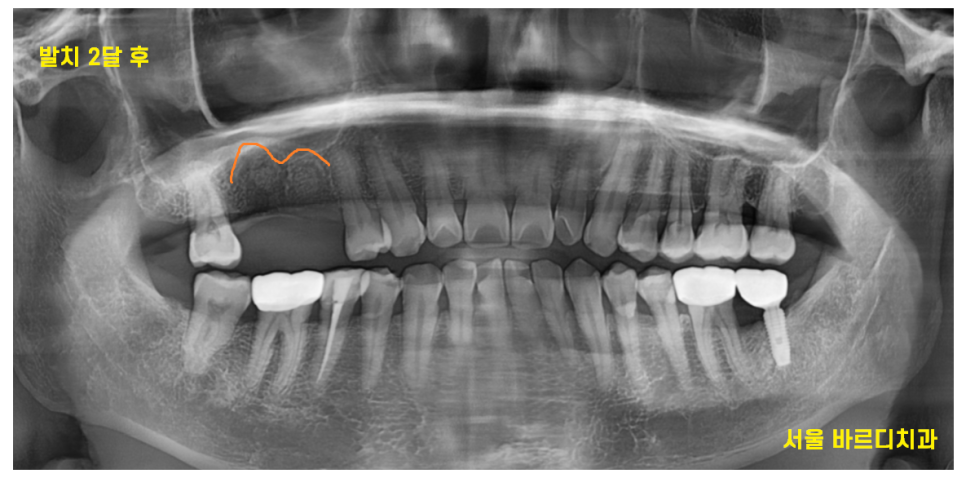

23.05.19

발치 후 뼈이식을 진행하고 두달 뒤

뼈가 차기는 했지만

아직 이 뺀 흔적이 보입니다.